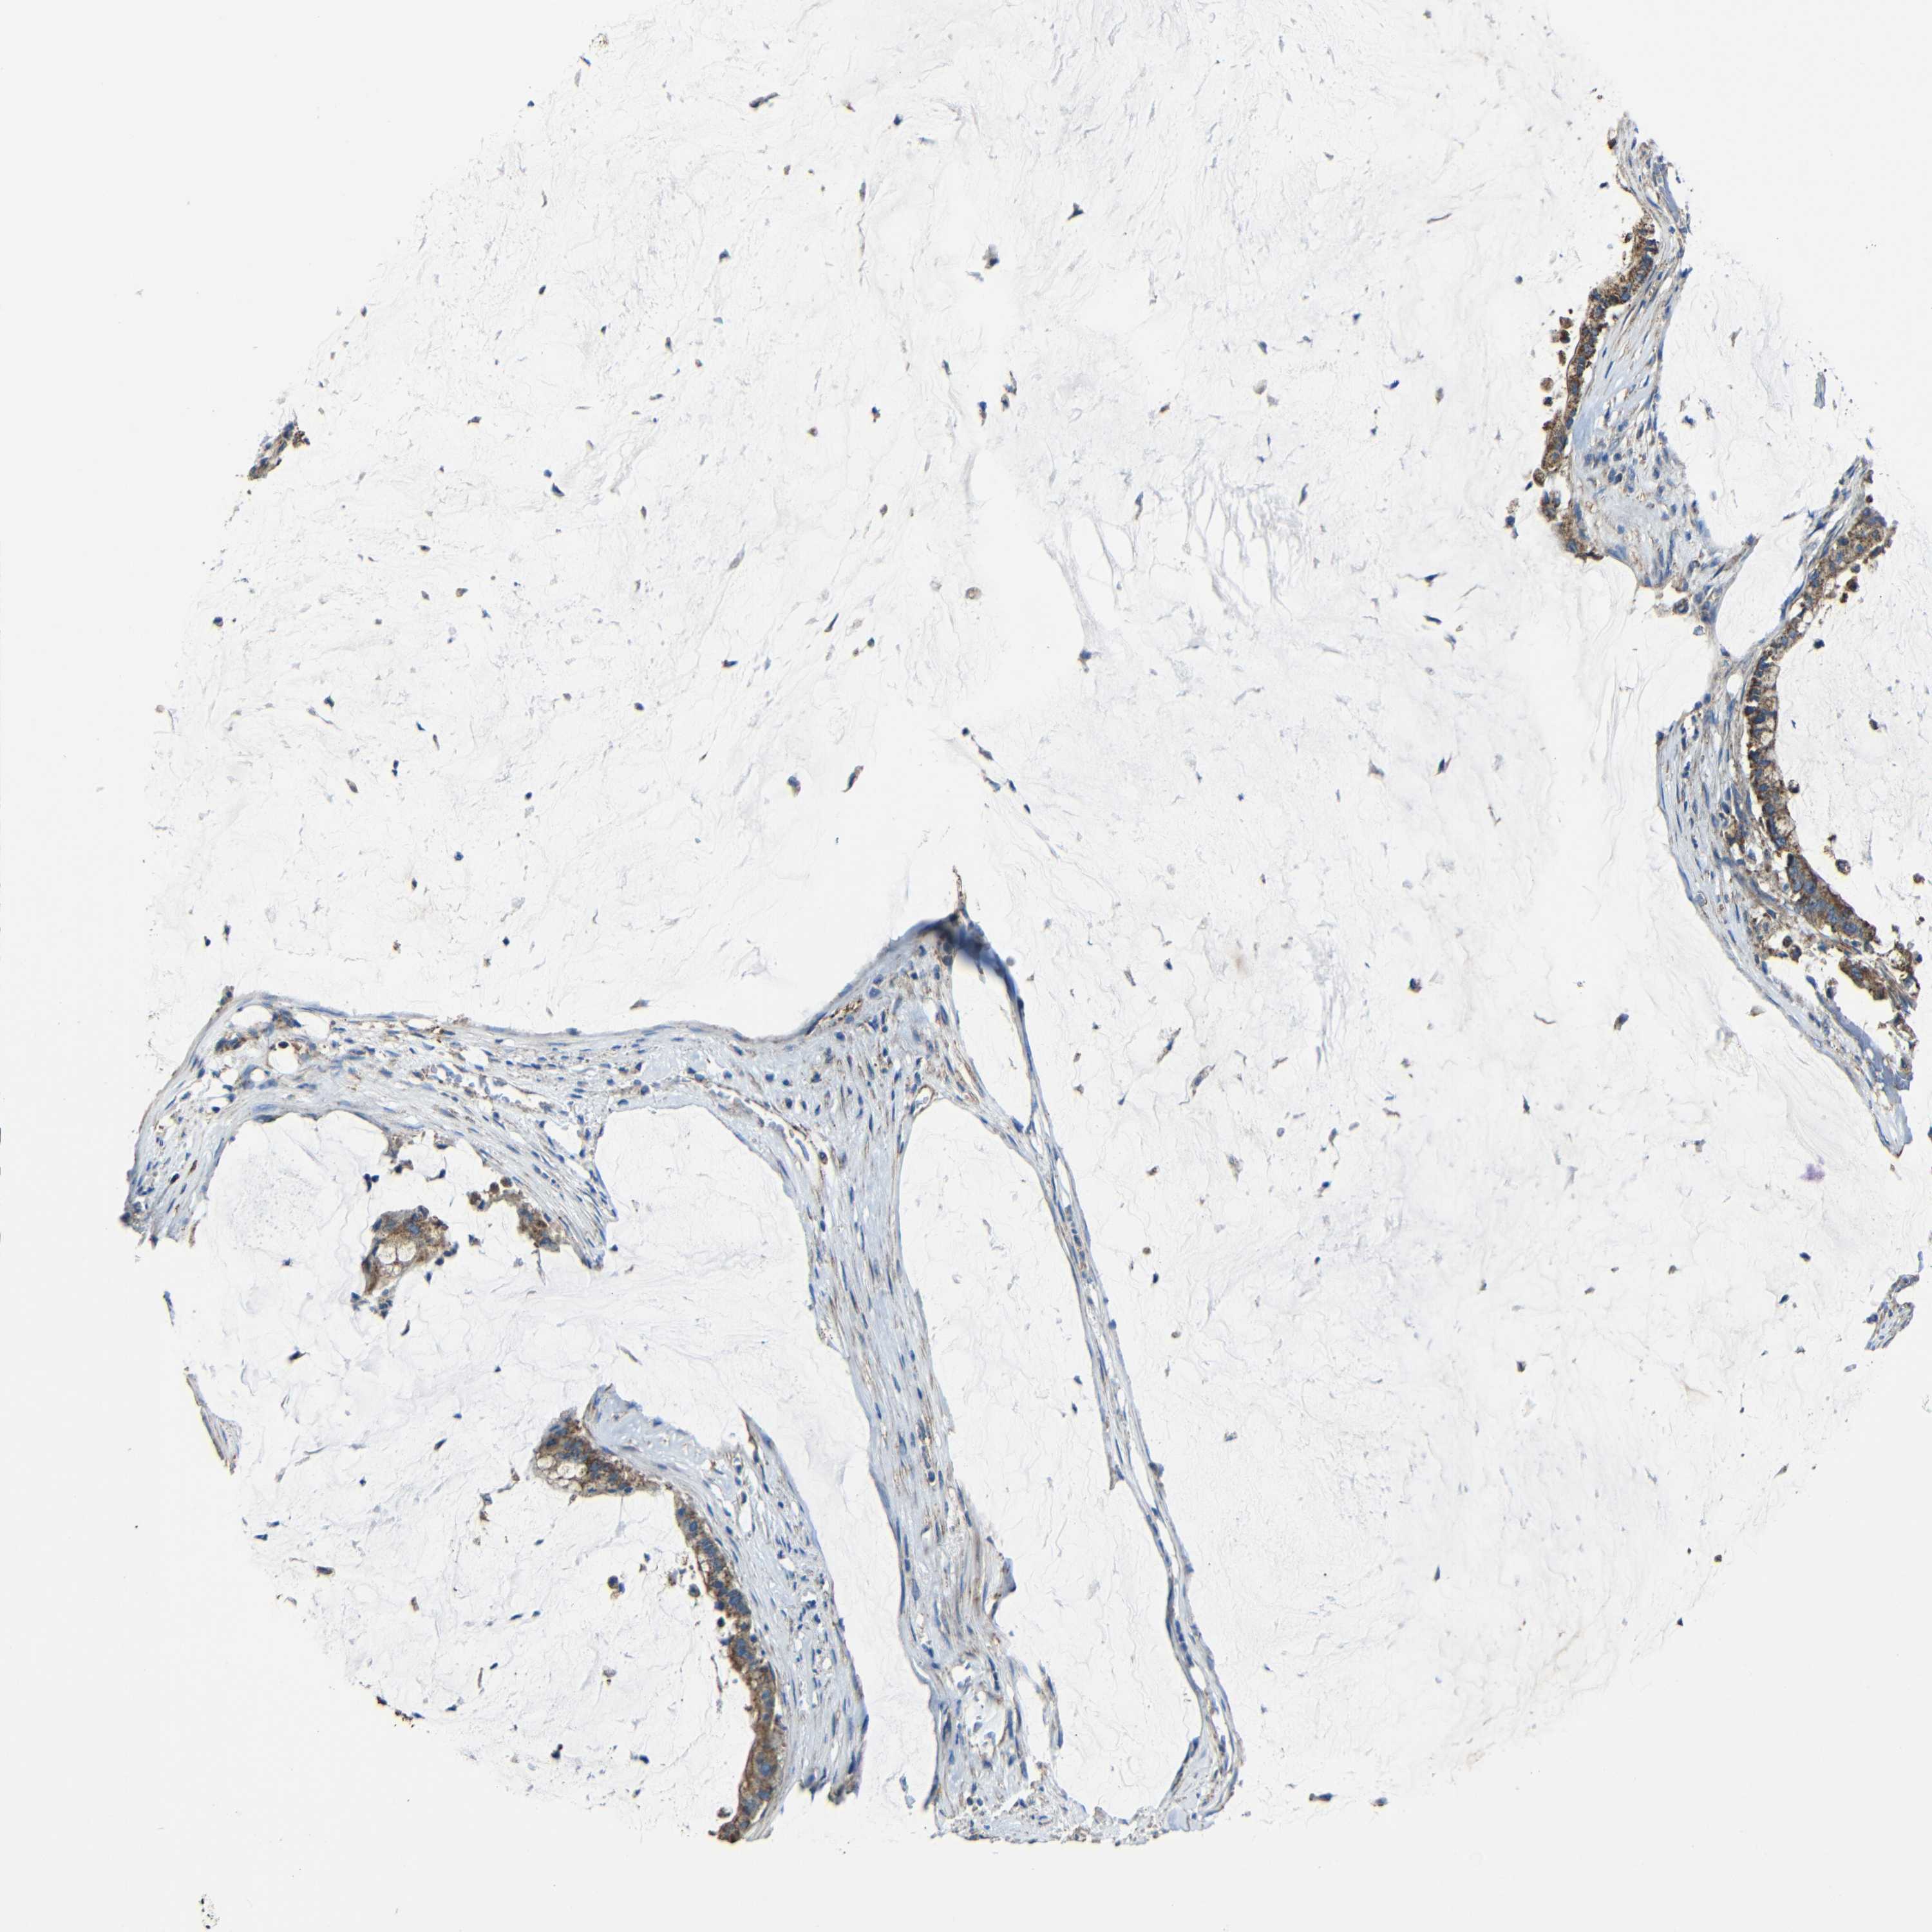

PANCREATIC CANCER - Protein expressioni

A mouse-over function shows sample information and annotation data. Click on an image to view it in a full screen mode. Samples can be filtered based on level of antibody staining by selecting one or several of the following categories: high, medium, low and not detected. The assay and annotation is described here.

Note that samples used for immunohistochemistry by the Human Protein Atlas do not correspond to samples in the TCGA dataset.

Antibody stainingi

Antibody staining in the annotated cell types in the current human tissue is reported as not detected, low, medium, or high, based on conventional immunohistochemistry profiling in selected tissues. This score is based on the combination of the staining intensity and fraction of stained cells.

Each image is clickable and will lead to virtual microscopy that enables deeper exploration of all samples and also displays staining intensity scores, fraction scores and subcellular localization as well as patient and tissue information for each sample.

Antibody HPA001552

Antibody HPA013335

Staining

High

Medium

Low

Not detected

Intensity

Strong

Moderate

Weak

Negative

Quantity

>75%

75%-25%

<25%

None

Location

Nuclear

Cytoplasmic/membranous

Cytoplasmic/membranous,nuclear

Adenocarcinoma, NOS

Adenocarcinoma, metastatic, NOS